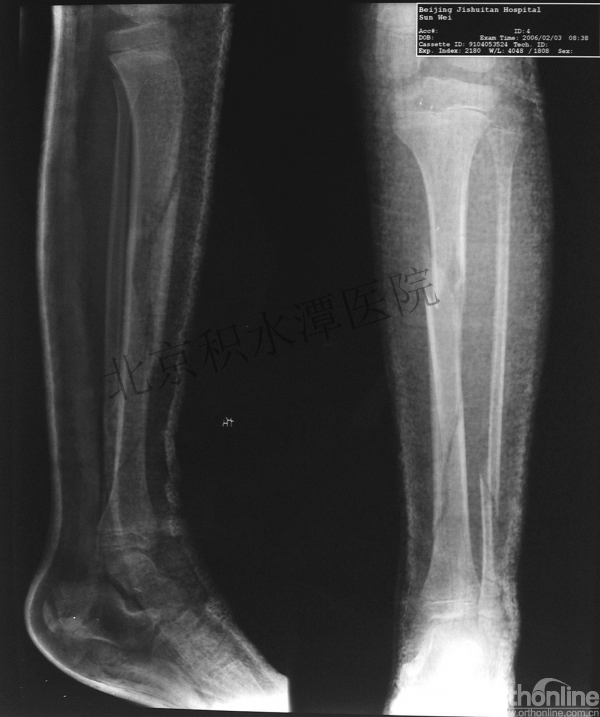

男孩、9岁,滑雪受伤,胫腓骨螺旋形骨折(粉碎性)

手法整复,石膏制动!

整复后7天

儿童具备强大的愈合潜力,同样也有极强的塑形能力

某种情况下,The best treatment is no treatment! 最佳治疗反而是不治疗!因为很多骨折依靠儿童强大的塑形能力和特点完全可以得到满意的结果!